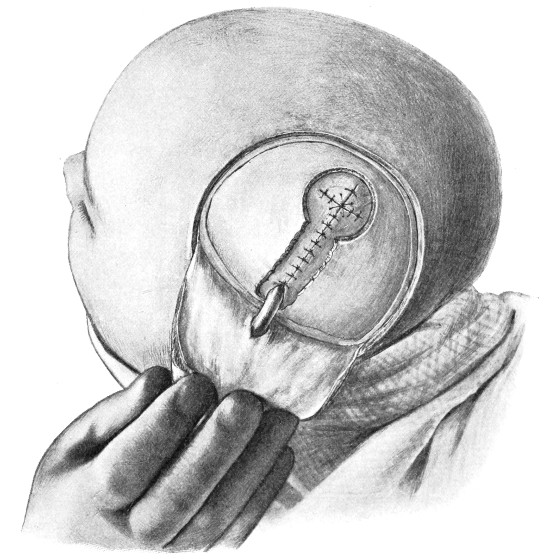

| 9 and 10. The technique of trephining | 22 |

Between these two trephine-holes the dura mater is separated from the bone and the special director introduced, entering at the one hole, emerging at the other, and lying throughout between the dura and the bone. The saw is now passed along the groove of the director, the handles affixed, and the bone intervening between the two trephine-holes divided, not straight out to the surface, but bevelled or cut in such an oblique manner that the bone-flap, when replaced, rests on a ledge (see Figs. 17-19). The sawing process[26] generates considerable heat, and the assistant should be instructed to keep up irrigation with saline solution or sterilized water. The sawing is carried out by steady side-to-side traction, without jerks; if the saw breaks, the special handle may be attached, thus obviating the necessity of introducing a new saw.

Fig. 18. Second Stage in the Formation of an Osteoplastic Flap. The bone-flap turned down and the dura mater exposed.

Fig. 19. Third Stage in the Formation of an Osteoplastic Flap. The dural flap turned down and the brain exposed. Note the relation of the scalp, bone, and dural incisions to one another.

The dura is now separated from the bone along the line of the two vertical incisions, and the visceral blade of de Vilbiss’s forceps insinuated beneath the bone, starting at one trephine-hole and working downwards to the lower limit of the incision. It is essential that the operator should be satisfied with the ‘morcellement’ of small portions of bone at each bite of the instrument. At the lower end of each[28] of the vertical incisions the forceps is directed inwards for 1⁄4 to 1⁄2 inch so as to weaken the base of the flap.

To lift up the osteoplastic flap, a stout elevator or spatula is introduced beneath the bone at its upper part, leverage applied, and, as soon as sufficient elevation has been attained, the dura mater carefully separated from the whole of the under aspect of the flap. The flap is then grasped at its upper part with both hands and, with a quick but forcible jerk, broken across at its base, the assistant at the same time aiding the correct linear fracture of the bone by a flat spatula applied to the outer aspect of the base of the flap. Insomuch as the flap is most usually framed in the parieto-temporal region—for the exposure of the motor area—the base of the flap, being formed from the squamous portion of the temporal bone, is comparatively weak. Fracture is then readily obtained. Under other circumstances the base may be sufficiently weakened by the application of the de Vilbiss forceps or by the use of the Gigli saw.

The bone-flap is thrown back and enveloped in gauze. Its basal region is examined for a possible injury to meningeal vessels. In the event of such complications the bleeding vessel is clipped, ligatured, or underrun. Possibly some branch of the anterior division of the middle meningeal artery, running in an osseous canal, may require to be controlled by foraminal occlusion—with a wooden match, bone peg, cotton-wool, or aseptic wax.

In comparing the relative advantages and disadvantages of craniectomy and craniotomy, although there are certain definite contra-indications to the latter method, yet craniotomy should always be carried out when the surgeon desires to expose a large surface area of brain, more especially in the exposure of a tumour diagnosed to lie in relation to the motor cortex. Even if the operator should be unsuccessful in his exploration, or, if finding the tumour, should deem it irremovable, the dura can be sewn up and the bone-flap replaced, resting on its bevelled edge, with little defect in the skull and a normal surface contour.